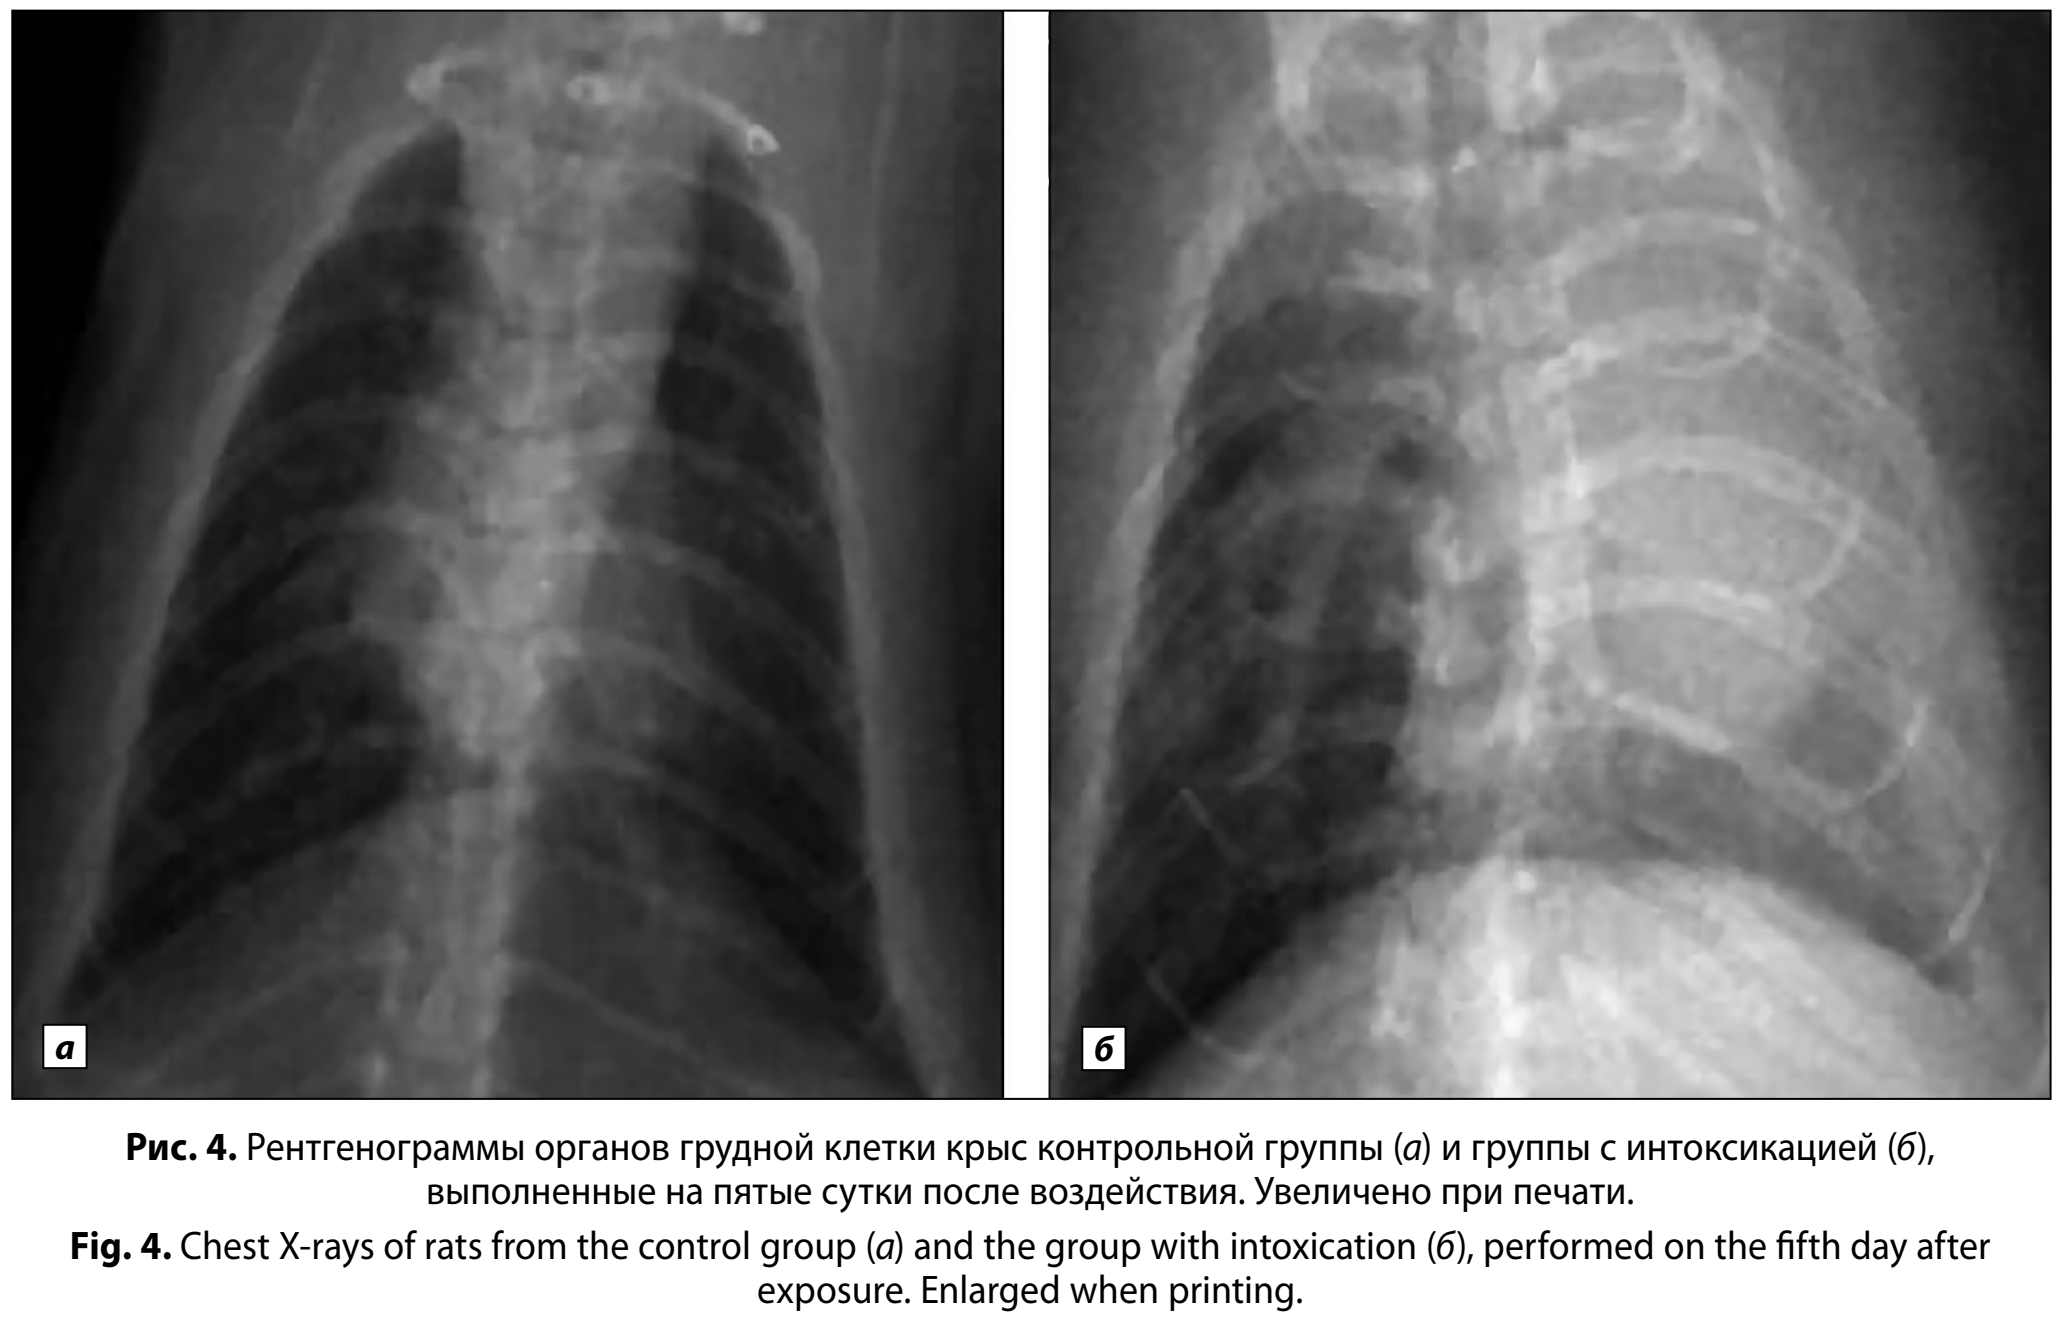

При проведении анализа рентгенограмм, полученных после воздействия, выявили значимые (p < 0,01) различия в частоте встречаемости очаговой инфильтрации у животных, подвергшихся воздействию бензина, по сравнению с животными контрольной группы. На 1-е сутки у 20 ± 9% животных группы с интоксикацией наблюдали усиление лёгочного рисунка с очаговой инфильтрацией в верхних сегментах лёгких, тогда как в контроле патологические изменения отсутствовали (рис. 3, а, б). К 5-м суткам доля особей с рентгенологическими признаками поражения составила 50 ± 12% и была выше (p < 0,001) по сравнению с контролем (рис. 4, а, б).